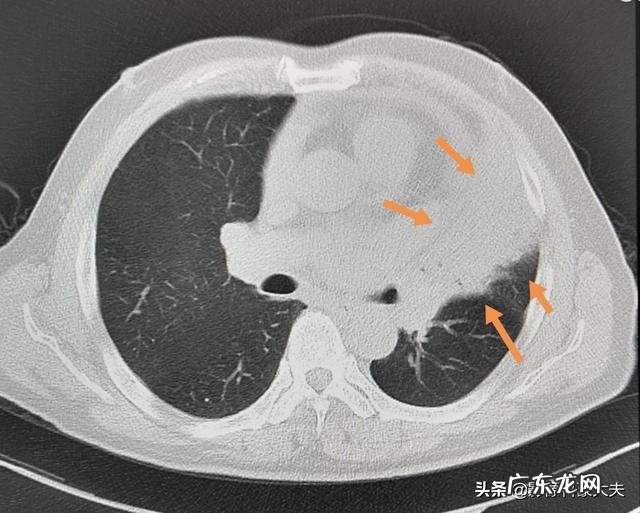

像这位50多岁的男子,咳嗽一个月,左肺上叶肺不张,体积缩小,密度增高(肺内气体被吸收) 。进一步增强CT和支气管镜检查,发现中心型肺鳞癌: